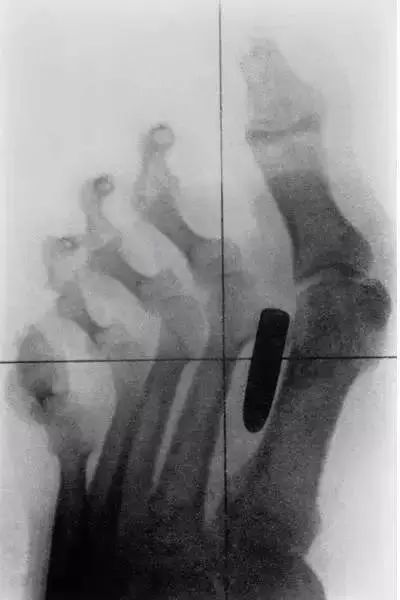

15、这张X光片上,这个成年男性的中指被一根钉子穿透。